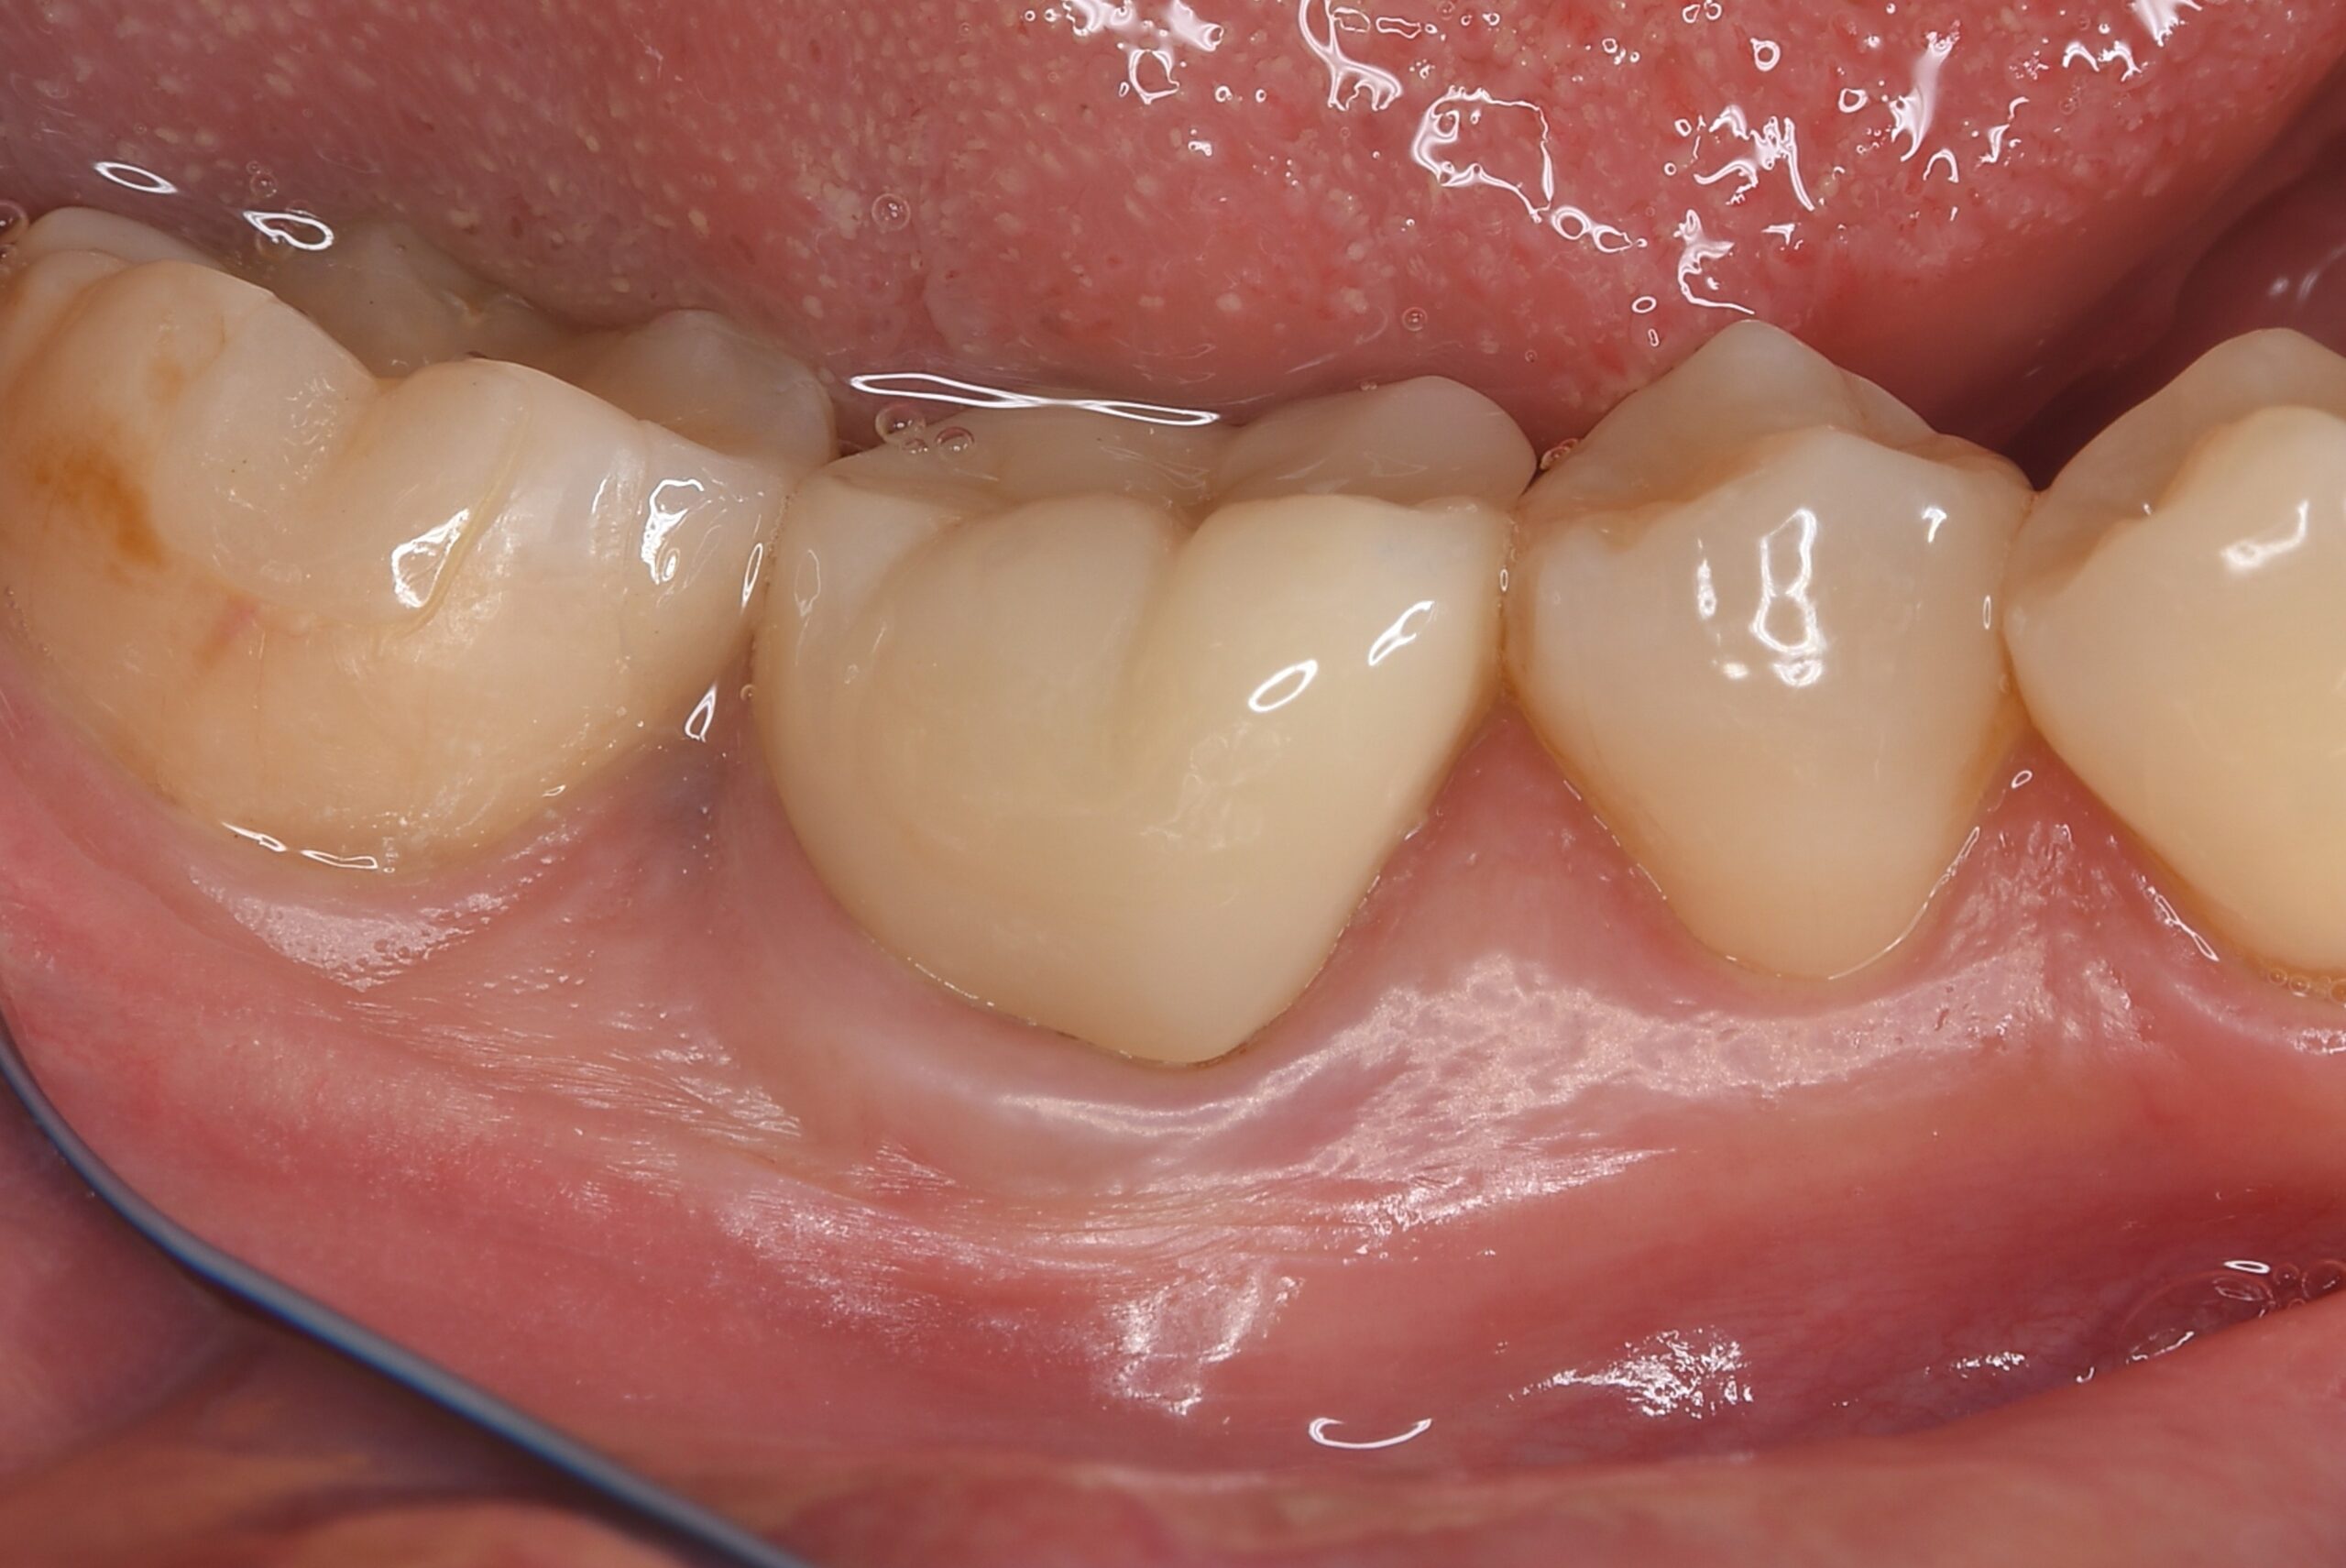

BEFORE |

AFTER |

炎症を起こしてからかなり時間が経っているためか、神経が確認できない程に歯髄狭窄を起こしていました。 ラバーダム防湿とマイクロスコープを使用して丁寧に治療を行いました。 再根管治療のため、殺菌性があり歯を補強することのできる根管充填材料を使用しています。 |